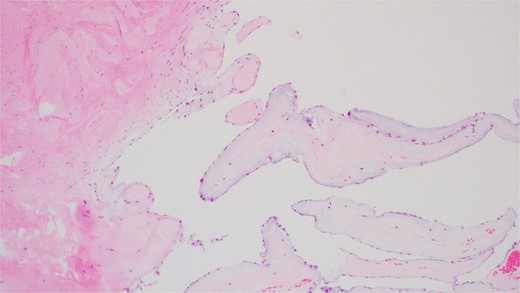

A 55-year-old man with hypertension and hyperlipidemia presented to our hospital with non-ST-segment myocardial infarction (NSTEMI). He was a smoker with no family history of heart disease. Patient was having class III angina for the previous 6 months but never sought medical help. He had no shortness of breath and no history of previous cerebrovascular accident (CVA). The patient underwent coronary angiogram that showed triple vessel disease with chronically occluded right coronary artery. Preoperative TTE showed left ventricular ejection fraction of 50% with mild mitral valve regurgitation and no aortic valve disease (Fig. 1A). Chest radiography was normal and his preoperative blood tests including C-reactive protein, Erythrocyte sedimentation rate (ESR), and complete blood count were normal. Blood cultures were negative. Patient underwent CABG during the same hospitalization due to his recurrent chest pain. Intraoperative TEE (Fig. 1B) showed a mass in the undersurface (ventricular side) of the non-coronary cusp (NCC) of aortic valve with normal valve function (tri leaflet valve). The differential diagnosis at that time included vegetation, calcification, or tumor. Median sternotomy was performed with ascending aorta and right atrial venous cannulation. CABG was performed with left internal mammary artery anastomosis to left anterior descending artery and reverse saphenous vein graft anastomosis to obtuse marginal artery. The aortic valve was exposed through transverse aortotomy and the mass was visualized in the ventricular side of NCC of aortic valve measuring 6 × 5 mm. It was white in color, rounded with some fronds (Fig. 2). The aortic valve was tri-leaflet valve with some calcifications noted in the other two cusps. The mass was then shaved off the valve and sent to histopathology. The leaflet was intact, and the aortic valve was tested and was normal with no regurgitation. Patient tolerated the procedure well and was weaned from cardiopulmonary bypass with small dose of Dobutamine. TEE at the end of operation showed well-functioning aortic valve with no aortic regurgitation. Patient was extubated 7 hours postoperatively and he had uncomplicated postoperative recovery and was discharged home 1 week postoperatively on dual antiplatelet therapy (Aspirin and Clopidegrol). Pathology report of the aortic mass (Fig. 3) showed 0.6 × 0.5 × 0.4 cm PFE (microscopic section showed multiple branching fronds and paucicellular avascular fibro elastic tissue lined by a single layer of endocardium). Patient remained well and asymptomatic at 3 months postoperatively.

Hematoxylin and Eosin (H&E) stain of the tumor showing multiple branching fronds of paucicellular fibroelastic tissue lined by a single endocardium. Magnification power ×100.